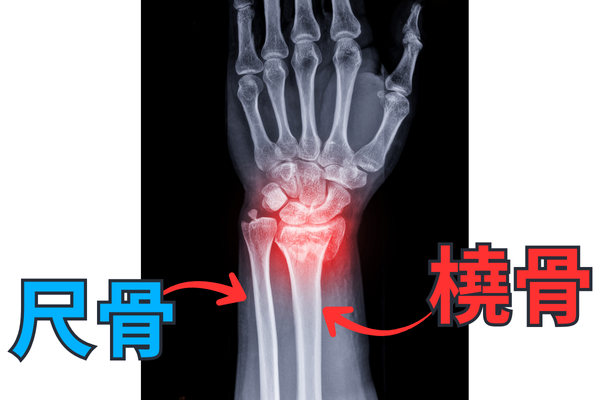

前腕には橈骨と尺骨があります。

四つ這いをしたときにはどちらに体重を乗せるのが良いでしょうか?

正解は橈骨です。

橈骨のほうが太いですし、全身の連動を考えたときには橈骨のほうが良いです。

逆に尺骨に乗ったらどうでしょうか?

腕では上腕三頭筋に力が入り、三角筋にも力が入って、肩がモリっと出てきます。

これでは全身が連動が切れてしまい、背骨も動きにくくなってしまいます。

橈骨に乗るのが正解です。

そうなれば肩甲骨もしっかり動いてくれます。